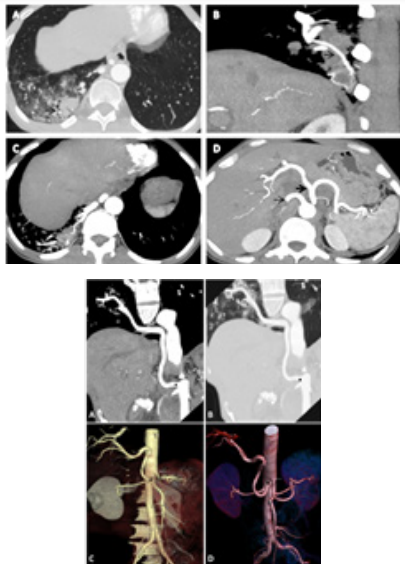

There is also soft tissue consolidation with adjacent ground glass densities noted in a posteromedial segment of the right lower lobe (Figure 2A). The involved part of the lung was supplied by a separate branch arising from the abdominal aorta (just below the coeliac trunk), (Figure 2(B–D)) seen in the arterial phase suggestive of intra-lobar pulmonary sequestration.

Figure 2Soft tissue consolidation with adjacent ground glass densities noted in a posteromedial segment of the right lower lobe seen in the arterial phase suggestive of intra-lobar pulmonary sequestration.

Pryce coined the term sequestration in 1946 to describe a disconnected bronchopulmonary mass or cyst with an anomalous systemic artery.3 There are two primary types of sequestration, i.e., intra-lobar sequestration(ILS) and extra-lobar sequestration (ELS).ILS accounts for approximately 75% of all sequestrations. Most patients present with cough, sputum production, and recurrent pneumonia. Over 50% are symptomatic by the age of 20. Many cases (98%) occur in the lower lobes, usually on the left side.ELS accounts for the rest, 25%. A majority of cases of ELS (61 %) occur in the first six months of life, often presenting on the first day of life with dyspnea, cyanosis, and feeding difficulties.4 Asymptomatic pulmonary sequestrations are typically found incidentally on imaging, as in our case, it was found incidentally in visualized lung field when the CT abdomen was taken. To confirm this, CT angiography was done, but in our case, the afferent vessel feeding the pulmonary sequestration was visualized through post-contrast CT.